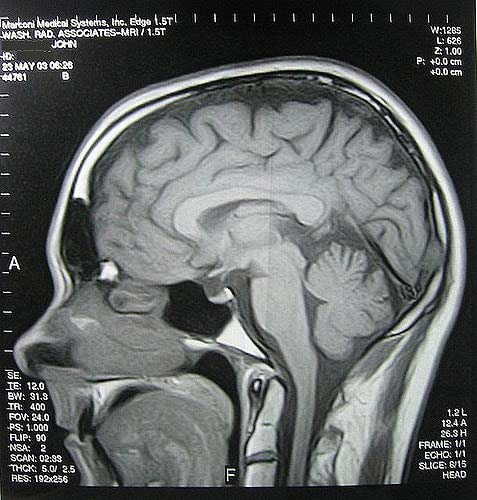

- МРТ. Выявляет патологии сосудов или наличие опухолей. МРТ всего тела покажет наличие нарушений в вашем организме, связанных с сосудами и нервной системой.

Это означает, что в большинстве случаев МРТ помогает поставить правильный диагноз;